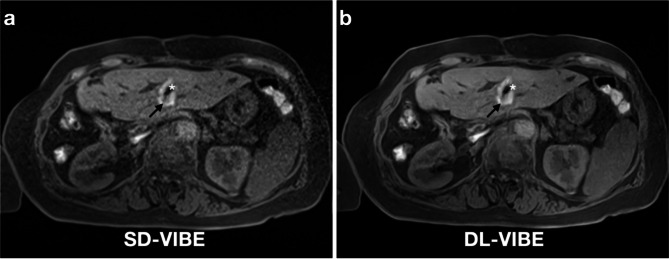

Objective: This study evaluates the impact of deep learning-enhanced T1-weighted VIBE sequences (DL-VIBE) on image quality and procedural parameters during MR-guided thermoablation of liver malignancies, compared to standard VIBE (SD-VIBE).

Methods: Between September 2021 and February 2023, 34 patients (mean age: 65.4 years; 13 women) underwent MR-guided microwave ablation on a 1.5 T scanner. Intraprocedural SD-VIBE sequences were retrospectively processed with a deep learning algorithm (DL-VIBE) to reduce noise and enhance sharpness. Two interventional radiologists independently assessed image quality, noise, artifacts, sharpness, diagnostic confidence, and procedural parameters using a 5-point Likert scale. Interrater agreement was analyzed, and noise maps were created to assess signal-to-noise ratio improvements.

Results: DL-VIBE significantly improved image quality, reduced artifacts and noise, and enhanced sharpness of liver contours and portal vein branches compared to SD-VIBE (p < 0.01). Procedural metrics, including needle tip detectability, confidence in needle positioning, and ablation zone assessment, were significantly better with DL-VIBE (p < 0.01). Interrater agreement was high (Cohen κ = 0.86). Reconstruction times for DL-VIBE were 3 s for k-space reconstruction and 1 s for superresolution processing. Simulated acquisition modifications reduced breath-hold duration by approximately 2 s.

Conclusion: DL-VIBE enhances image quality during MR-guided thermal ablation while improving efficiency through reduced processing and acquisition times.